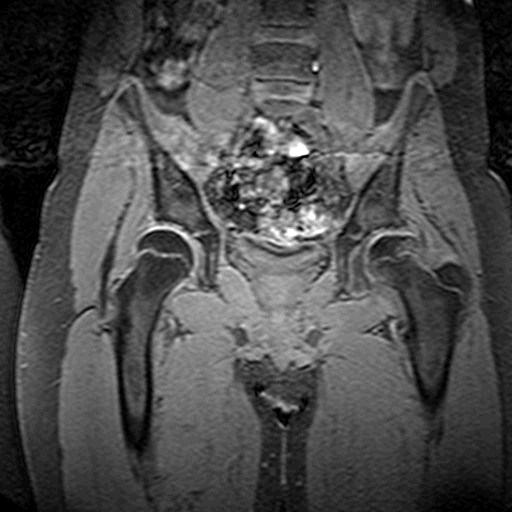

Images d’IRM

Retour sommaire

Illustration 13 : Séquence T1. Fragmentation et coxa plana à gauche. Notez le cartilage qui apparaît en gris clair autour des têtes fémorales et du cotyle. (source : hôpital Robert Debré).

Illustration 14 : Séquence T2. On note une fracture sous-chondrale et une excentration de la tête fémorale gauche. L'épanchement apparaît en blanc entre le cotyle et la tête.(source : hôpital Robert Debré)

Illustration 15 : Séquence dynamique avec injection de gadolinium. La tête gauche se reconstruit. On visualise la vascularisation de la tête gauche en noir. La ligne de démarcation entre le fémur et la tête du fémur n'est pas nette : la revascularisation se fait par le fémur ce qui est de très mauvais pronostic.(source : hôpital Robert Debré).

Illustration 13 : Séquence T1. Fragmentation et coxa plana à gauche

Illustration 14 : Séquence T2. Fracture sous-chondrale et excentration de la tête fémorale gauche

Illustration 15 : Séquence dynamique avec injection de gadolinium